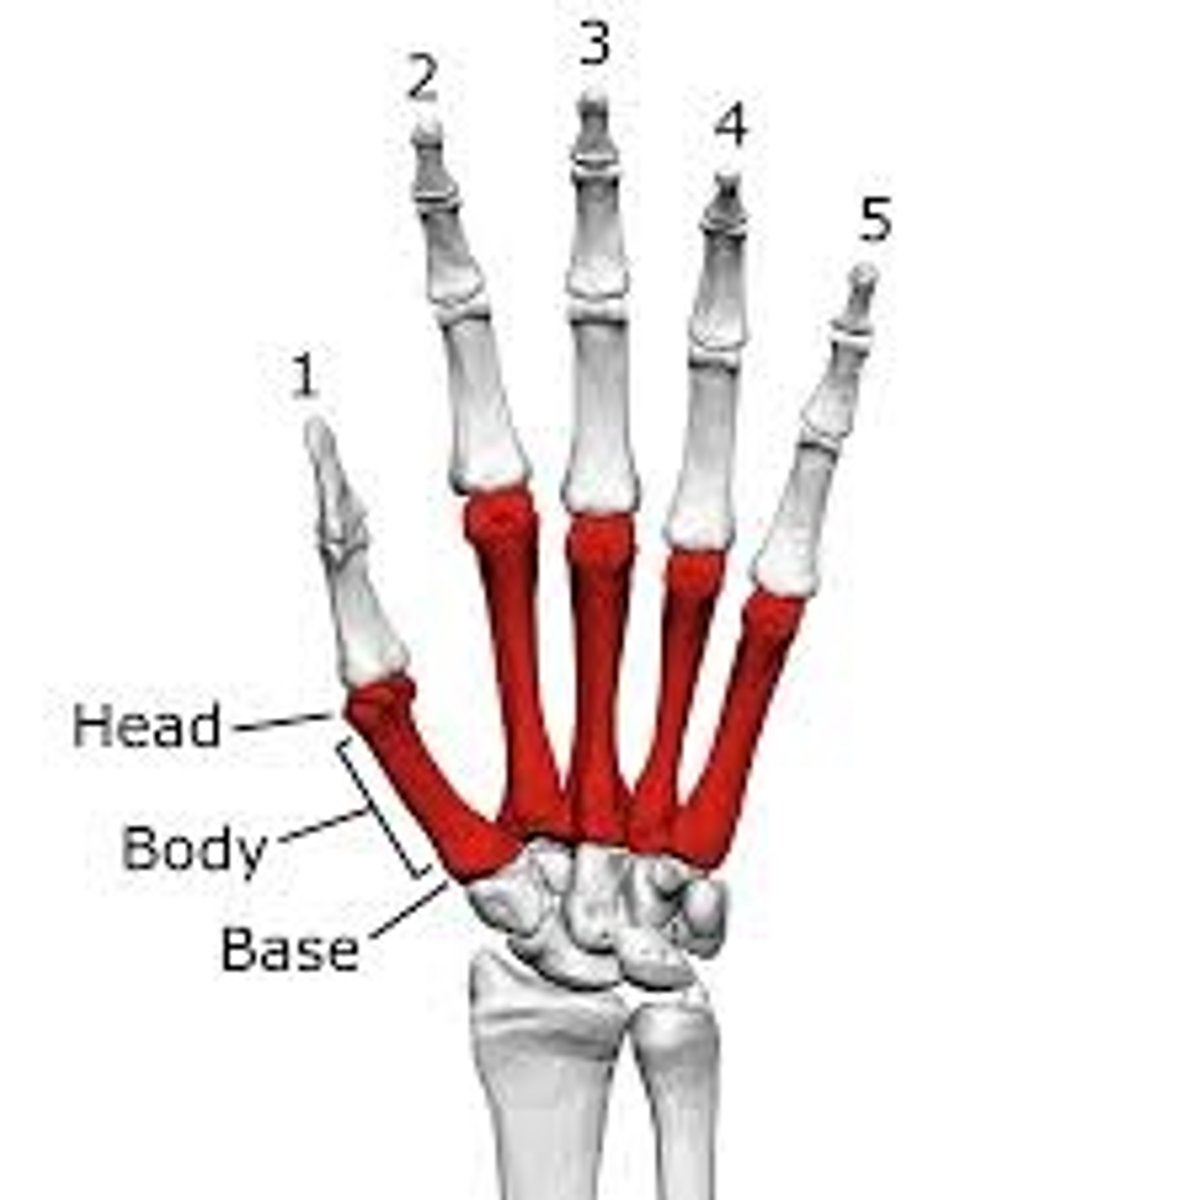

Metacarpals

What is the term of the bones highlighted in green?